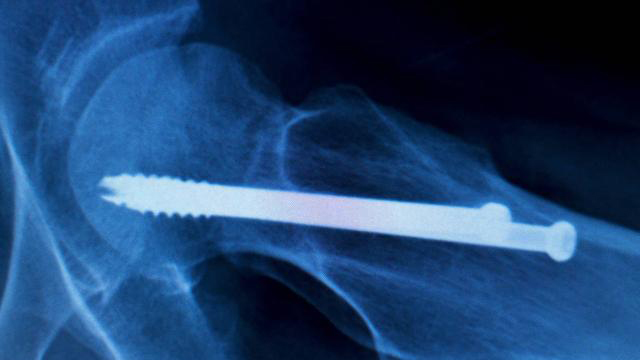

(2)对于I型II型但年龄较大的患者,或者年龄小于65岁的III型IV型患者,前者长期卧床容易肺部感染、下肢深静脉血栓、压疮等并发症,则多主张内固定手术治疗,有利于患者康复。术后1个月至3个月复查,根据愈合情况考虑下地活动。

(3)Garden III型及IV型骨折患者,年龄较大者,多采用人工股骨头置换术或人工全髋关节置换术。术后三天即可下地拄拐行走,保护期也是三个月。Garden III型及IV型骨折患者,年龄较小者,可采用带血运的骨瓣植骨内固定术(常用缝匠肌蒂髂骨瓣植骨术和旋髂深动脉髂骨瓣植骨术)。三个月左右即可弃拐自行。